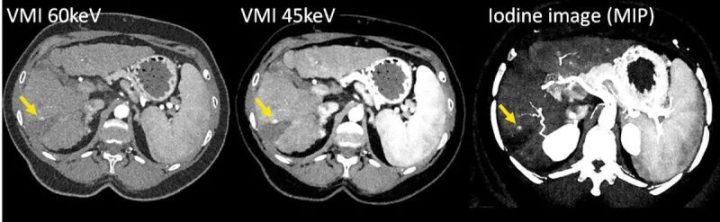

有几项临床研究对PCD-CT的VMI图像质量、CNR以及与EID-CT相比对患者造成的相关辐射剂量进行了调查。一组50名患有肝转移的肿瘤患者使用PCD-CT在120 kV电压下进行扫描,另一组50名患者使用EID-CT在自动选择管电压的情况下进行扫描,其中大部分扫描建议使用100 kV电压。与EID-CT的多色图像相比,PCD-CT的VMI在70 keV时显示出更低的图像噪点,在辐射剂量相似的情况下,40-70 keV范围内的CNR始终更高(PCD-CT的CTDIvol为6.7 mGy,EID-CT为6.4 mGy)。此外,在低keV下,低血管化肝转移灶的清晰度明显更高,与低体重指数患者相比,高体重指数患者可从PCD-CT中获益,因为图像噪声和病灶清晰度都得到了保留。在另一项研究中,40名患者在第三代DSCT的高螺距模式下接受了胸腹主动脉CTA。通过自动选择管电压(参考电压100kV)来选择最佳管电压。每位患者都在管电压为120 kV的PCD-CT上接受了辐射剂量匹配的后续扫描,并在40、45、50和55 keV下重建了VMI。与EID-CT图像相比,40和45 keV PCD-CT的平均CNR明显更高,超重患者的CNR增益更高。在主观图像分析中,考虑到40和45 keV的图像噪声增加,45至50 keV的VMI被认为是最佳折衷。在其他研究中也观察到碘CNR在极低keV(如40 keV)时最高,但由于40 keV时图像噪声较高,诊断时首选稍高的keV(如50 keV)的趋势。在一项对39名门静脉期接受增强腹部PCD-CT的患者进行的比较研究中,作者发现在50 keV下对VMI进行标准化重建的效果最佳,与EID-CT相比,在相同辐射剂量下,主观图像质量相似,CNR明显更高。图10显示了腹部CT扫描的临床实例。在对80名疑似肺栓塞(PE)患者进行的PCD-CT检查中,50 keV的VMI的主观PE可见度最高。对于冠状动脉CTA,在模型评估和对10名患者的研究中,如果结合高水平的迭代重建(QIR3和QIR4),40 keV的VMI更受青睐。

图10 用PCD-DSCT(120 kV、144×0.4 mm、CTDIvol = 4.8 mGy)扫描的肝硬化和消融后肿瘤复发患者的CT图像。随着VMI(左侧和中间)的KeV水平降低,碘CNR增加,肿瘤复发(箭头)变得更加明显。碘图像(右)可以量化碘吸收。